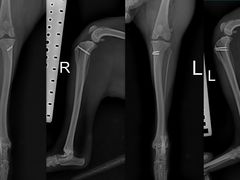

• 东莞宠友24H宠物中心医院·转诊夜诊·异宠(新河北路院)

灵活能干嘭当蝠 | 24-04-01

报错

• -东莞宠友24H宠物中心医院·转诊夜诊·异宠(新河北路院)